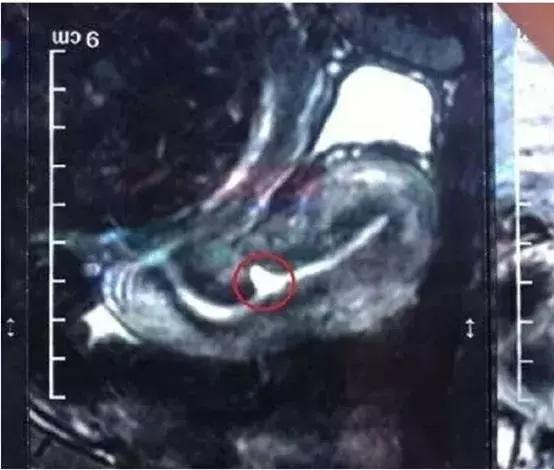

子宫憩室的诊断

根据患者阴道不规则出血、不孕等情况,结合影像学检查做出诊断。

1. 宫腔碘油造影

在子宫下段或者宫颈管前壁见龛影;

5. 腹腔镜、阴式手术

无论什么样的治疗方案,结合患者自身的情况,是否有再生育的要求等综合判断,消除憩室、恢复正常的组织结构,减少憩室内物质的聚集和生成,使经血及分泌物顺利流出为目的。采用外科手术治疗需要结合磁共振检查充分评估切口的大小、部位、与膀胱的关系等,力争找到创伤最小、治疗效果最佳的途径。